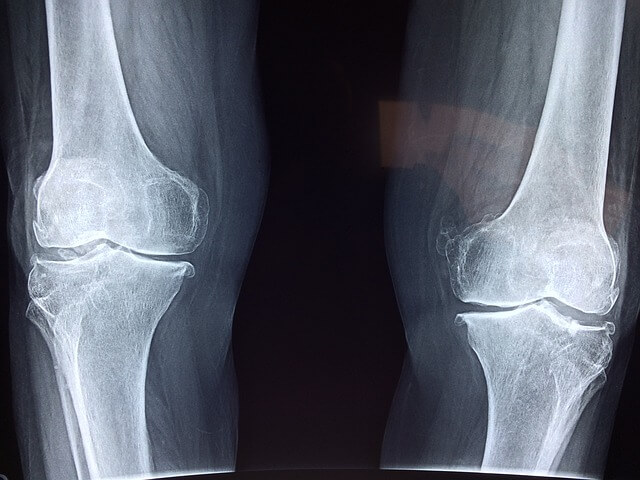

1) 우리의 무릎 관절 안쪽과 바깥쪽에 있는 반달 모양의 연골(반월상 연골)은, 무릎의 관절을 보호하고, 외부로부터의 충격을 흡수하거나 분산하는 역할을 해야 합니다. 그런데 반월상 연골이 그 역할을 감당해내지 못하면서 무릎을 구부릴 때 통증이 발생하게 됩니다

3) 무릎 연골은 무릎의 위쪽 뼈와 아래쪽 뼈의 충격이나 마찰을 줄여주는 역할을 합니다. 그런데 연골이 손상되어 닳아 없어지면서 무릎을 구부릴 때 뼈와 뼈가 서로 맞붙으면서 통증을 일으킵니다